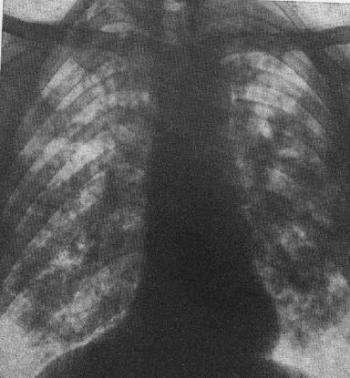

A Mycobacterium törzsnek patogén és nem patogén tagjai is vannak. A M. tuberculosis és M. bovis emberre patogének. A tuberculosis világszerte elterjedt, endémiás betegség és a világ népességének egyharmadát érinti. A tüdő tuberculosis gyakorisága növekszik az immundefficienciákkal, az alultápláltsággal, a kábítószer-fogyasztással és az AIDS-sel kapcsolatos problémák miatt. Bár a pulmonalis tuberculosis klinikuma kívül esik e könyv terjedelmén egy tbc-s beteg tüdő-röntgenfelvétele látható a 4.17. ábrán.

4.17. ábra. Tbc-s beteg mellkas-röntgenfevétele

A tuberculosis kezelése (management). Az orális tuberculosis gyanújával jelentkező beteg teljes kivizsgálást igényel, mind tüdőre, mind egyéb léziókra vonatkozóan. A betegség feltételezésének első pillanatában készüljön mellkas-röntgenfelvétel. A tuberculosis kezelése kívül esik az orális medicina területén, azt tüdőgyógyász vagy fertőző betegségekkel foglalkozó szakember végezze.